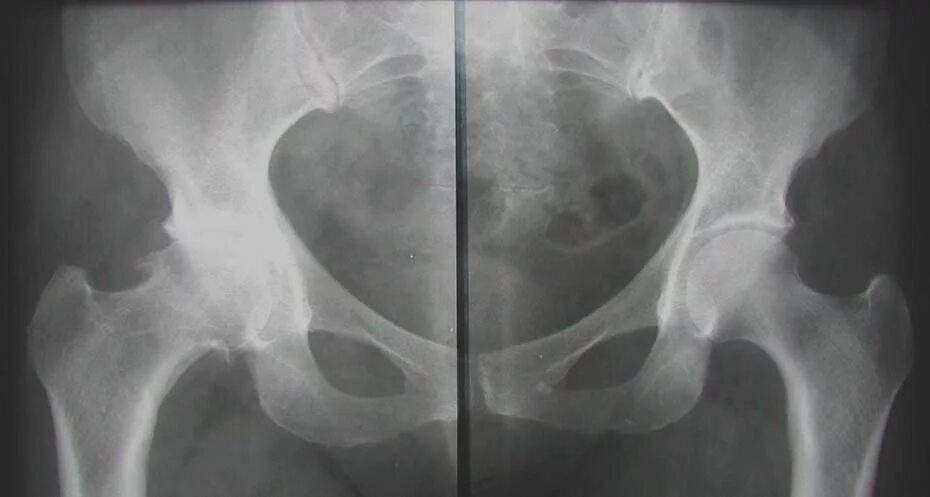

Коксартроз тазобедренного 1 степени симптомы